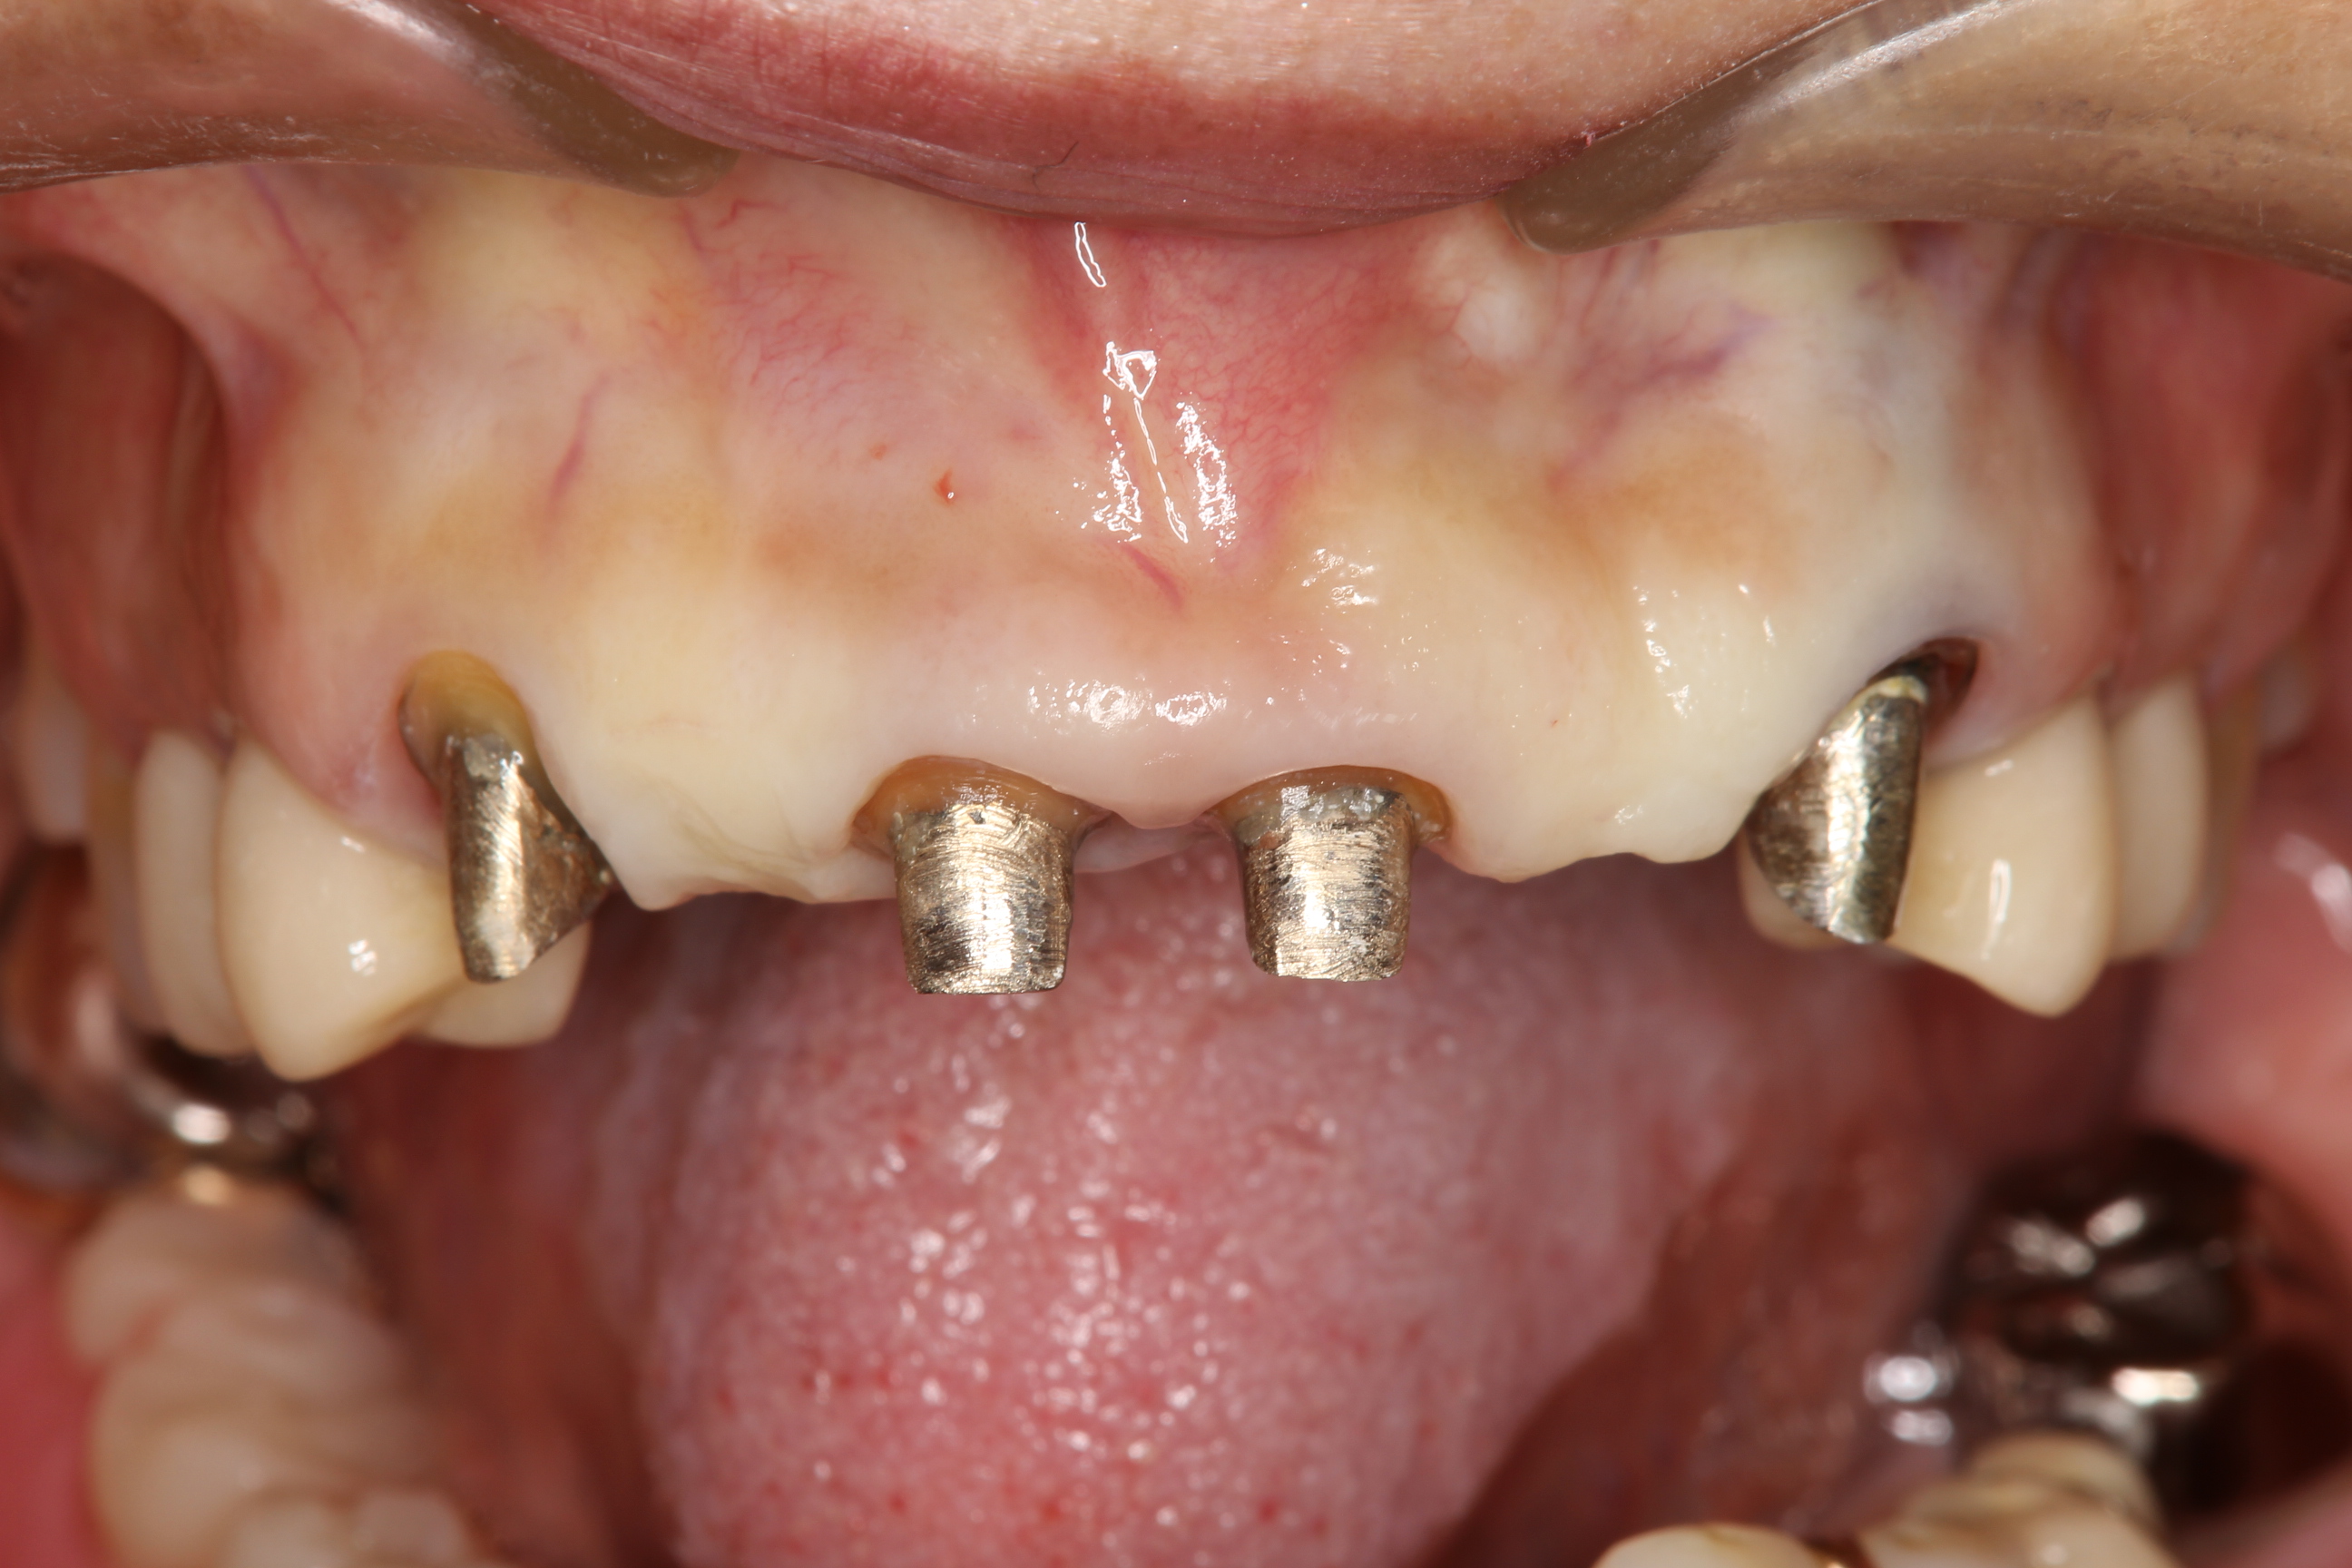

すべての被せ物や根の治療をし直し、口腔内のリコンストラクション(噛み合わせや見た目の再構築)を治療をしている患者さん。

上顎の歯は、ほぼすべての歯が仮歯になっており、根の治療やコア(土台)の装着が済んだところです。

下の写真では、古いクラウンを除去し、元々の歯肉の形態に合わせて作った仮歯が装着されています。

ただ、患者さんと色々話をしてみると、前にクラウンを装着した時から真ん中の前歯2本(⇓)の長さが短くて気になっていたそうです。

確かに、両隣の前歯(側切歯や犬歯)と比べると短いですね。

歯の長さを少し長くするためには、歯肉辺縁の位置を下げる必要があります。

上の術前の前歯(⇓)と比較して、1mmほど歯冠が長くなっています。

1mmでどれだけ変わるんだ?と思われる方もいらっしゃると思いますが、歯冠の長さと幅のバランスが良くなり、このように受ける印象が全く異なります。